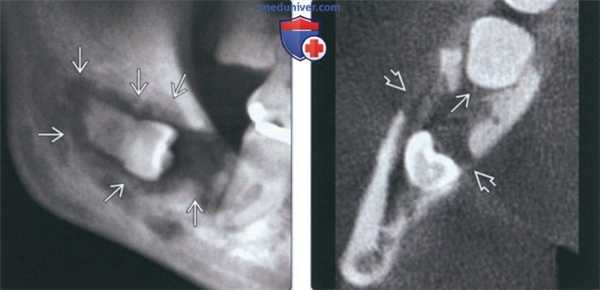

(Слева) На панорамной рентгенограмме определяется ЦМР, связанный с импактным 3-м моляром нижней челюсти справа. Опухоль выглядит как хорошо отграниченное просветление не правильной формы, связанное с коронкой и продолжающееся к корню. Эту опухоль, возникшую, вероятно, в зубной кисте или ке-ратокисте, можно спутать с остеомиелитом.

(Справа) На аксиальной КЛКТ у этого же пациента определяется распространение опухоли к пространству периодонтальной связки второго моляра. Обратите внимание на деструкцию кортикальной пластинки.

(Слева) На КЛКТ (профильный срез) у этот же пациента определяется хорошо отграниченное поражение в области коронки зуба. Нижний и язычный край имеют инфильтративный характер, щечная кортикальная пла стинка разрушена. Обратите внимание на интактный нижнече люстной канал внизу.

(Справа) На трехмерной реконструкции (КЛКТ, вид под углом) у этот же пациента визуализируется четкий мезиальный край кистозного образования, распространяющется в позадимолярную область.

3. КТ при центральном мукоэпидермоидном раке челюсти:

• Неровные края

• Деструкция кортикальной пластинки и поражение мягких тканей лучше обнаруживаются посредством КТ:

о Преимущественно в случаях длительно существующих опухолей